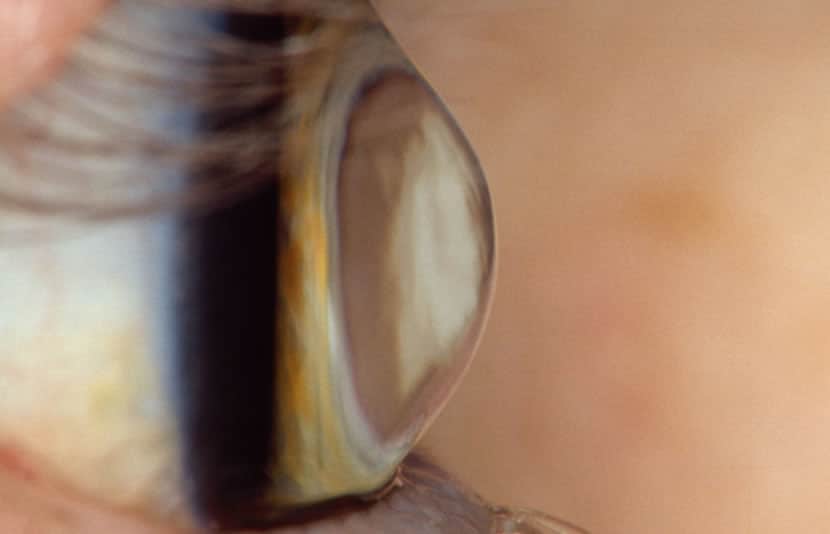

Keratoconus is a progressive eye disease in which the normally round cornea thins and begins to bulge into a cone-like shape. The cornea is the clear, central part of the surface of the eye, which is responsible for most of the eyes focusing power. In patients with keratoconus, the cone-shaped cornea deflects light and causes distorted vision.